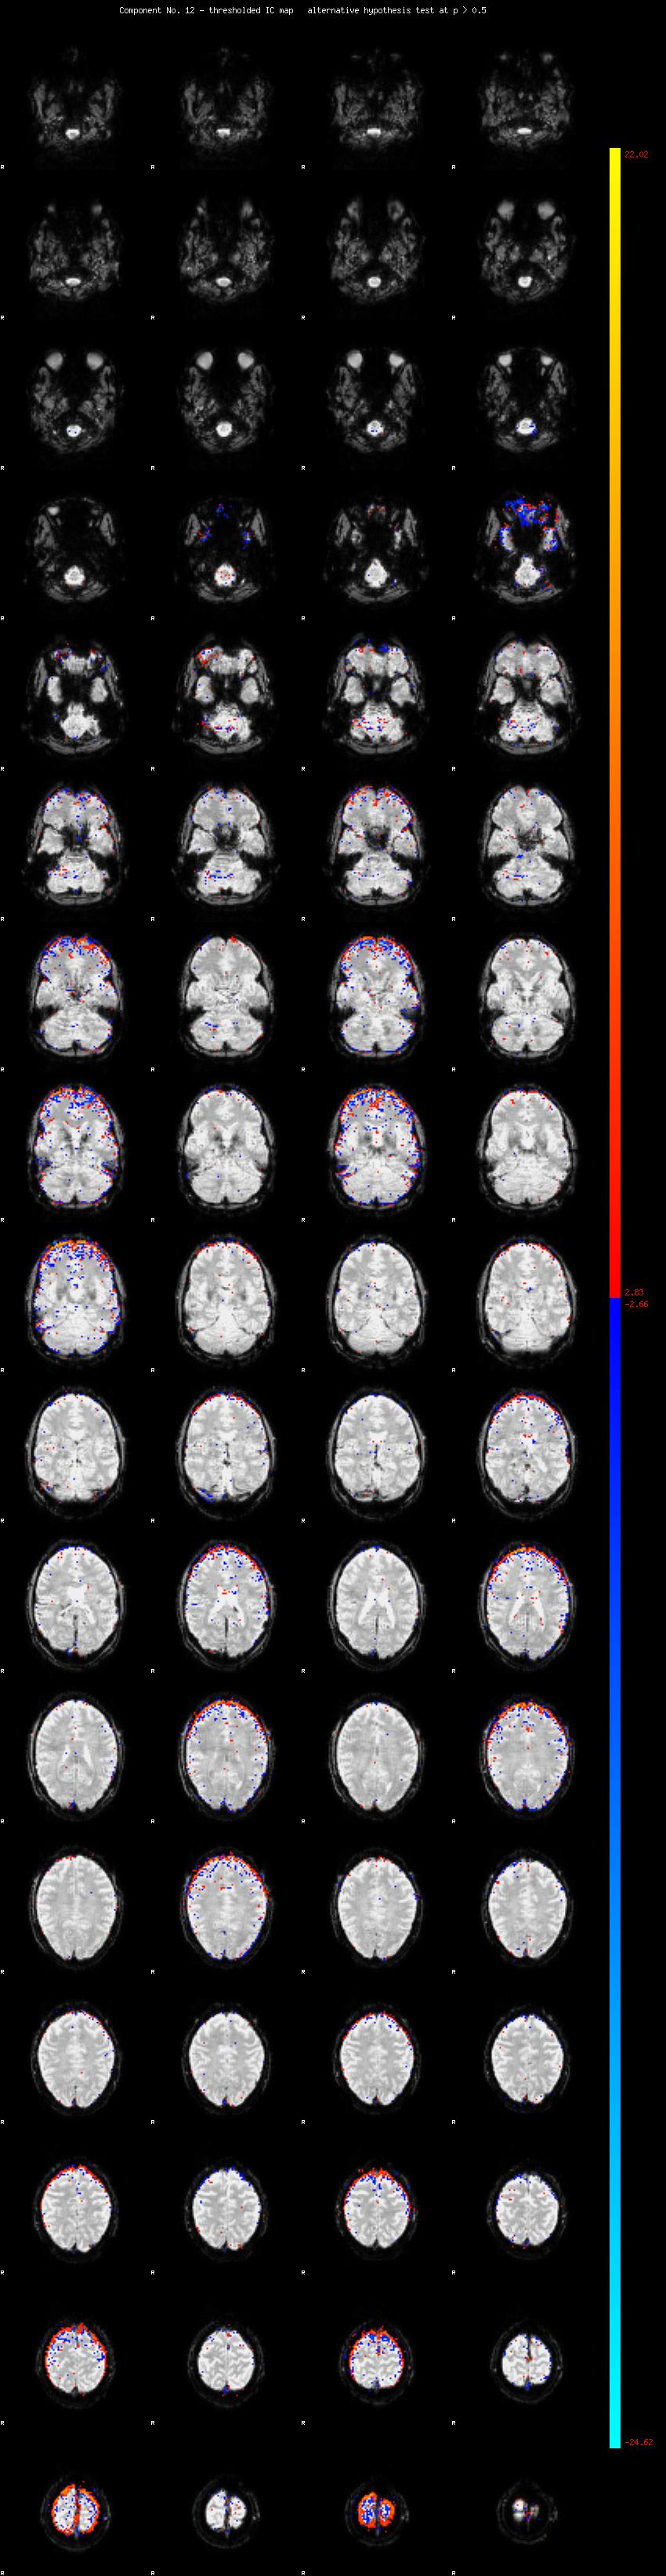

MELODIC Component 12

2.04 % of explained variance;     1.35 % of total variance